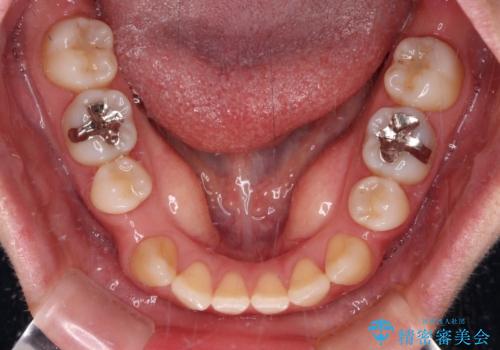

- 学生時代に行った抜歯矯正の後戻りで、隙間ができてしまったことを気にして来院された患者様です。

マウスピース矯正を検討されていましたが、後戻りの隙間が非常に大きく、奥歯を前方に移動させる必要があるため、ワイヤー装置にて矯正治療を行うこととしました。

舌の突出癖が非常に強く、その影響で隙間ができてしまったので、舌のトレーニングをしっかりと行っていただきました。